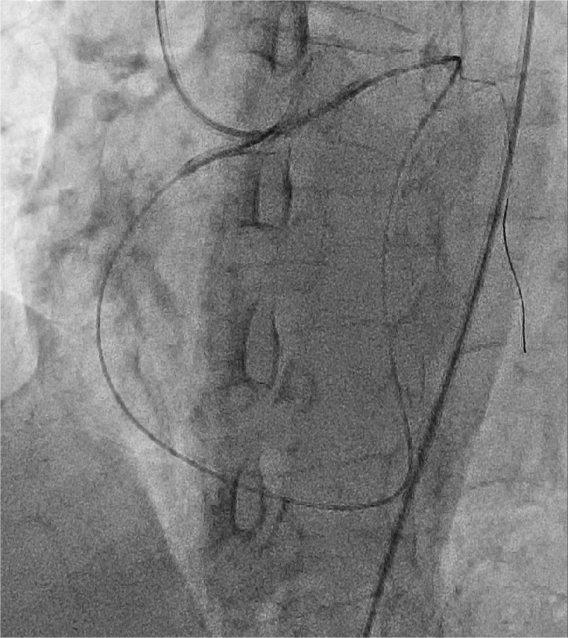

4月24日,朱舜明副主任医师为患者制定周密的手术方案和风险处理方案,朱舜明副主任医师、唐治国主治医师、张翔主治医师、张豪住院医师开展持续3小时的介入手术。术中穿刺桡动脉和股动脉,双路径同时造影显示病变血管完整结构,开展Reverse-CART技术,将逆向导丝送入正向指引导管,跟进微导管,交换导丝后用球囊扩张病变,沿逆向导丝送入双腔微导管至闭塞血管远端,沿双腔微导管送入正向工作导丝至右冠后降支,并退出逆向微导管和导丝,采用血管内超声精细评估病变情况,最终向右冠状动脉内植入3枚支架。术后多体位造影未见残余狭窄及贴壁不良,完美结束手术。

图2 Reverse-CART技术逆行导丝通过右冠病变血管,红色箭头:病变部位